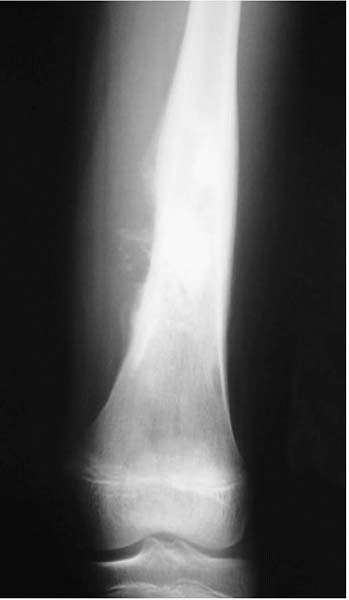

![]() |

|

▪ FIGURE 17-2

A femoral shaft fracture can often hide a pathologic lesion. This boy’s spiral distal third diaphyseal fracture was through a nonossifying fibroma. The lesion could not be well visualized until the fracture was reduced and studied in the operating room under fluoroscopy. |